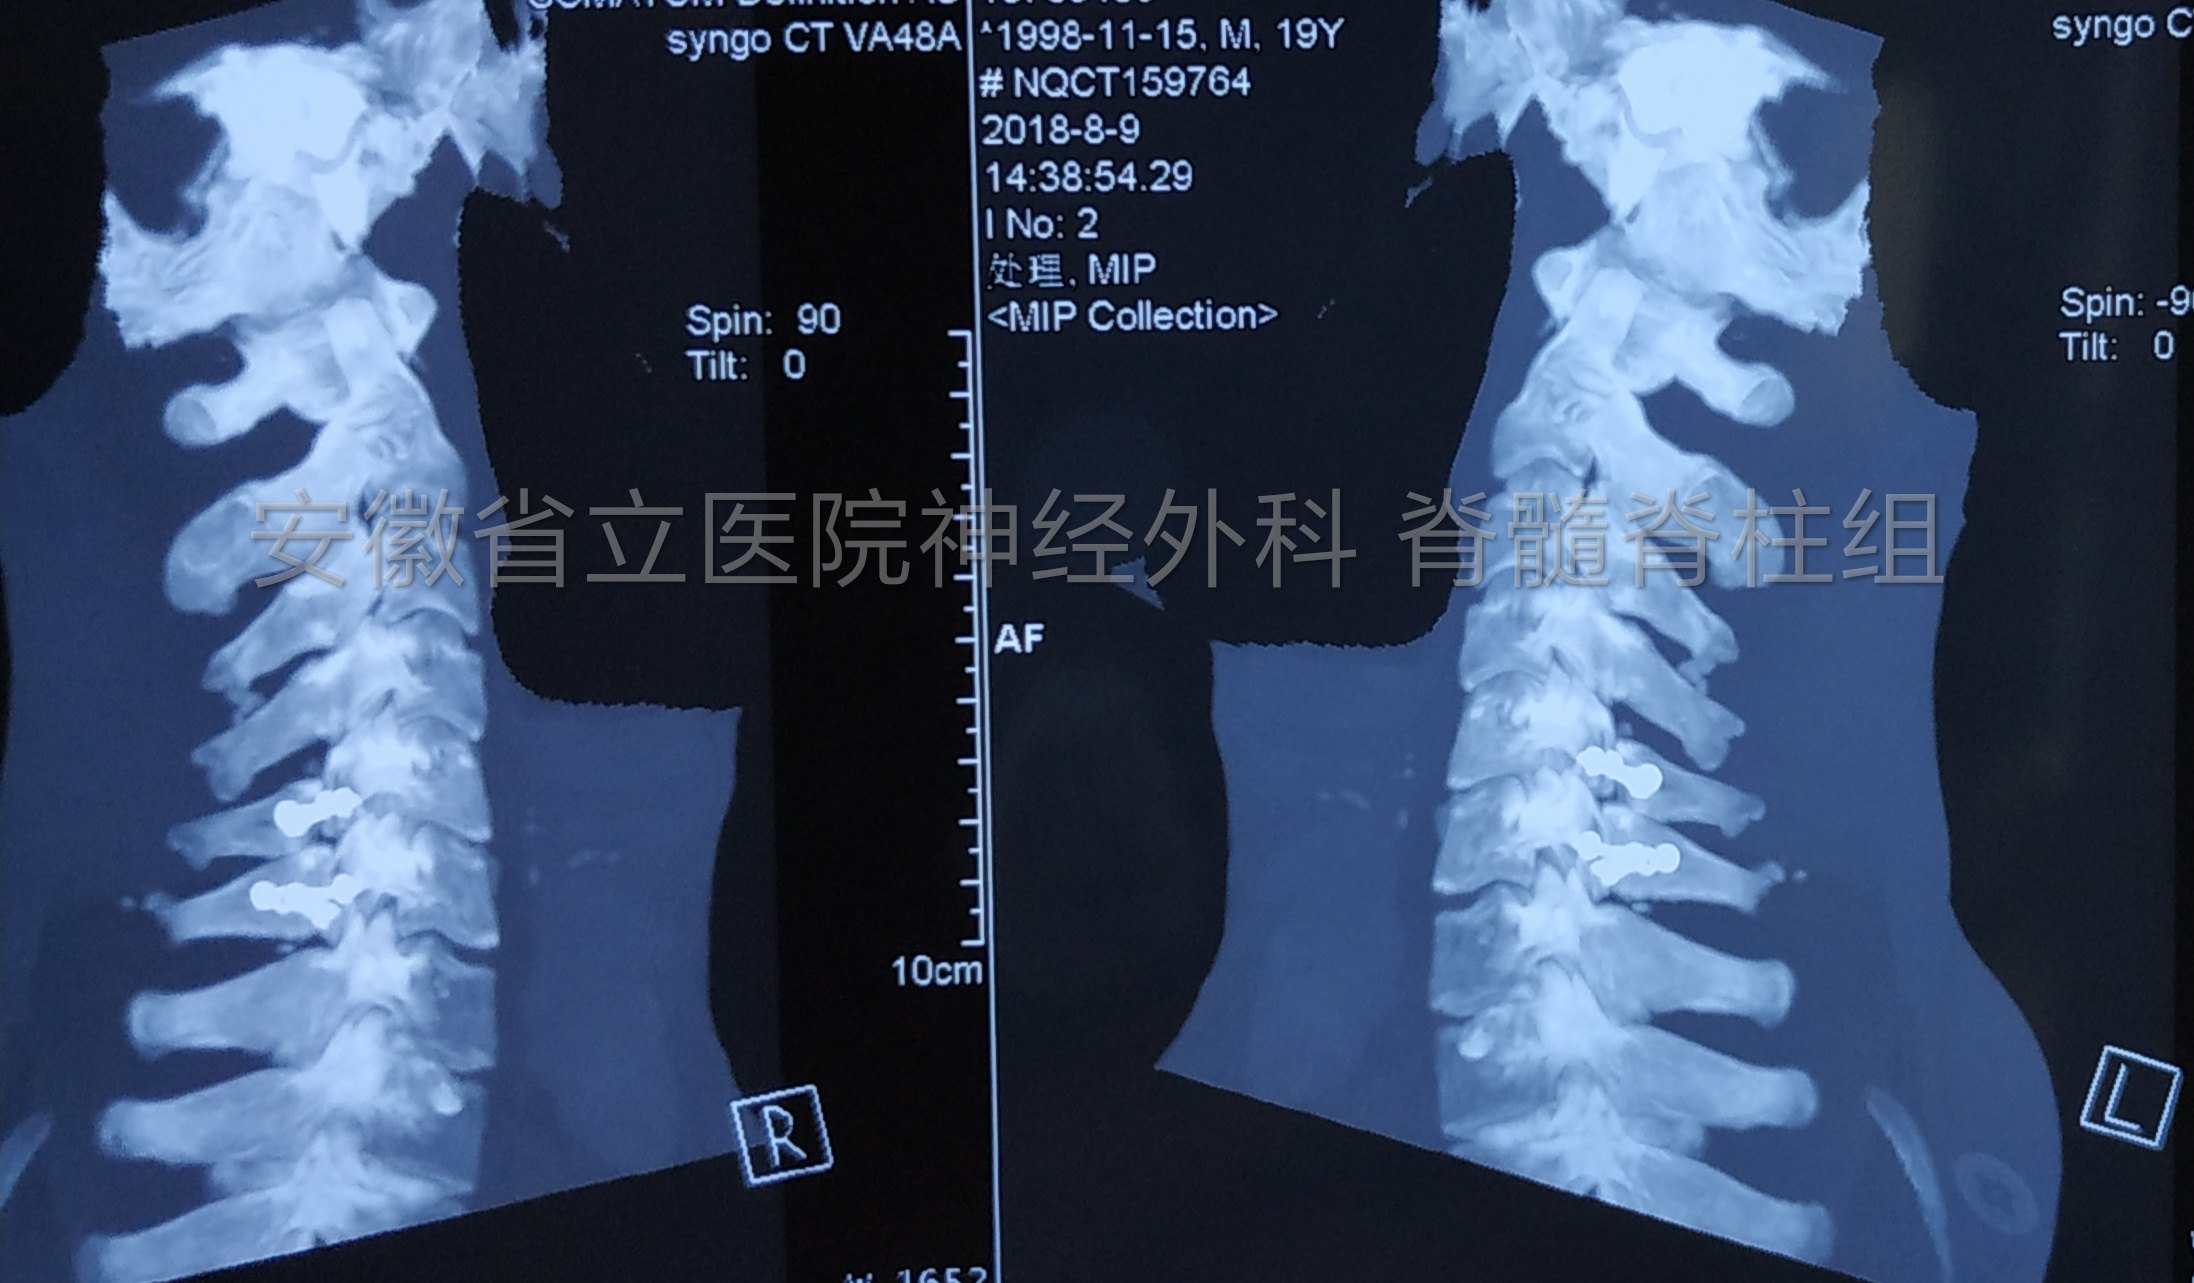

肿瘤切除后予以椎板骨质复位,术后复查显示椎管内肿瘤全切除,骨质复位良好,手术部位解剖完整,患者恢复快,脊柱稳定性得以保证。

椎管内肿瘤多数为良性,发现既需要手术治疗,手术疗效良好,但是要注意手术中保护脊髓神经功能,手术后恢复椎管解剖完整和脊柱稳定。

患者预后良好,术后肌力恢复很快,加强锻炼后肌肉萎缩逐渐恢复。